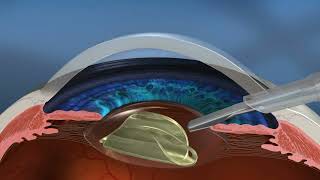

The LensX Laser Procedure (Cataract Surgery) video

LenSx Laser Cataract Surgery Video The LensX Laser Procedure (Cataract Surgery)

The LensX Laser Procedure (Cataract Surgery) Laser-Assisted Cataract Surgery (LenSx) with Dr. Grover Robinson IV